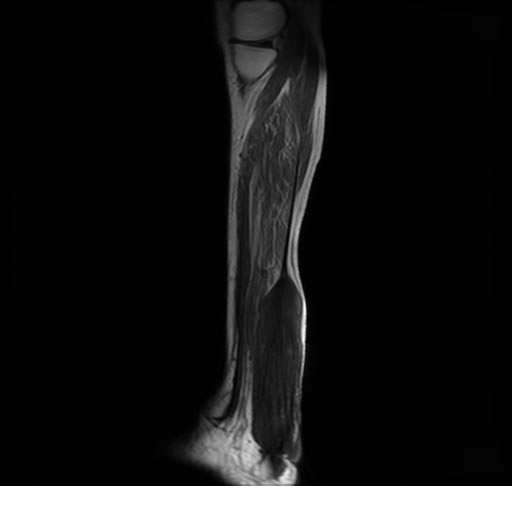

Se realiza estudio de MRI de pierna izquierda, utilizando secuencias Spin Echo y GRE en diferentes planos, se realiza angio MRI en fase arterial y venosa de pierna izquierda

El estudio demuestra masa a nivel de los músculos gemelos, más evidente en secuencia con pulso de saturación de grasa, en el estudio de angio resonancia de pierna la fase arterial no muestra ninguna anormalidad, en la fase venosa se observa acumulo del medio de contraste a este nivel.

Se concluye que se observa una masa de tejido muscular sumamente vascularizada compatible con un hemangioarcoma.